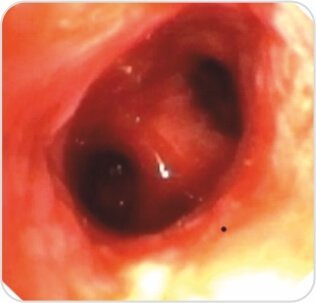

Procedure – Repair of TB stenosis was done by Rigid Bronchoscopy and Balloon Bronchoplasty.

Post procedure – Luminal patency was achieved with visualization of distal segmental bronchii.

Step 2